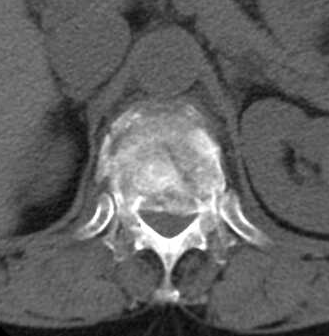

▲术前胸腰段三维CT检查提示:第12节胸椎爆裂性骨折伴椎管狭窄,椎管占位50%左右,第三节腰椎压缩性骨折,胸腰段后凸畸形。